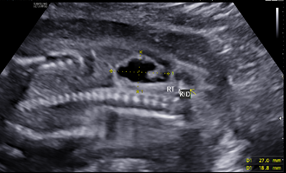

Figure 2 Moderate-to-marked bilateral renal hydronephrosis.

A 25-year-old G2P1001 at 19w2d presented for anatomic ultrasound. Routine prenatal genetic screening indicated an elevated risk for Down syndrome, 1:259. Her prenatal course was otherwise uncomplicated. Initial anatomical evaluation noted adequate amniotic fluid, a markedly distended fetal urinary bladder, moderate-to-marked bilateral renal hydronephrosis, a moderate degree of bilateral hydroureter, and bilateral renal cortical cysts, (Figures 1-4). Patient was sent for second opinion with secondary survey, within 1 week, denoting bladder outlet syndrome with oligohydramnios. A characteristic "keyhole" sign was noted (Figure 5). Patient initially elected for genetic non-invasive prenatal testing and later for genetic amniocentesis, the results of which revealed a normal karyotype/FISH/microarray. At the time of amniocentesis, bladder tap was performed and yielded 160cc of fluid for evaluation of renal function based on urine sodium, chloride, urine osmolality and calcium levels. At 22w3d patient presented for follow up sonographic evaluation; findings revealed significant fetal abdominal ascites, persistent oligohydramnios, a "bell-shaped" chest with only the left lung measurable, and the right lung poorly defined. Bilateral urinary tract dilation was again observed, with the right kidney measuring 2.0 x 3.0cm and the left kidney measuring 2.3 x 1.7cm. The kidneys were echogenic in nature and the parenchyma was thickened up to 7mm, with no pyramids visible. The bladder had severe thickening, measuring up to 7.7mm in diameter. The bladder measured 4.7 x 1.7cm with intraluminal calcifications noted both in the bladder and intestines. The patient was counseled on these new findings and concern for both pulmonary hypoplasia and possible poor renal function. The patient was given the option to proceed with fetal urinary evaluation for renal function and possible bladder shunt vs termination of pregnancy secondary to these findings; she elected for pregnancy termination.1–3

The presence of a posterior urethral valve prevents normal fetal micturition, resulting in bladder distension and subsequent distension of the ureters and kidneys. Diagnostic features of posterior urethral valves on sonography varies, but classically presents in male fetuses with fetal megacystis that may fill the entire abdomen, thickened bladder wall (>3mm) with prominent trabeculae, oligohydramnios, and bilateral hydronephrosis with hypoechoic renal parenchyma and/or cortical cysts that can indicate renal dysplasia. The best diagnostic clue is the presence of a dilated posterior urethra (“keyhole” sign) . While not always seen, its presence, suggests the diagnosis of PUV. These findings however, may be found in other urinary tract conditions. Megacystis is defined as a longitudinal bladder diameter (LBD) > 7mm in the first trimester. However, after the first trimester, it is most commonly defined as failure of bladder emptying during a 45min period of ultrasound examination.5